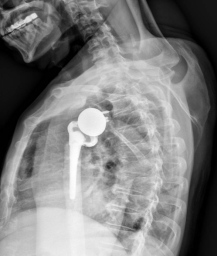

术后X线片